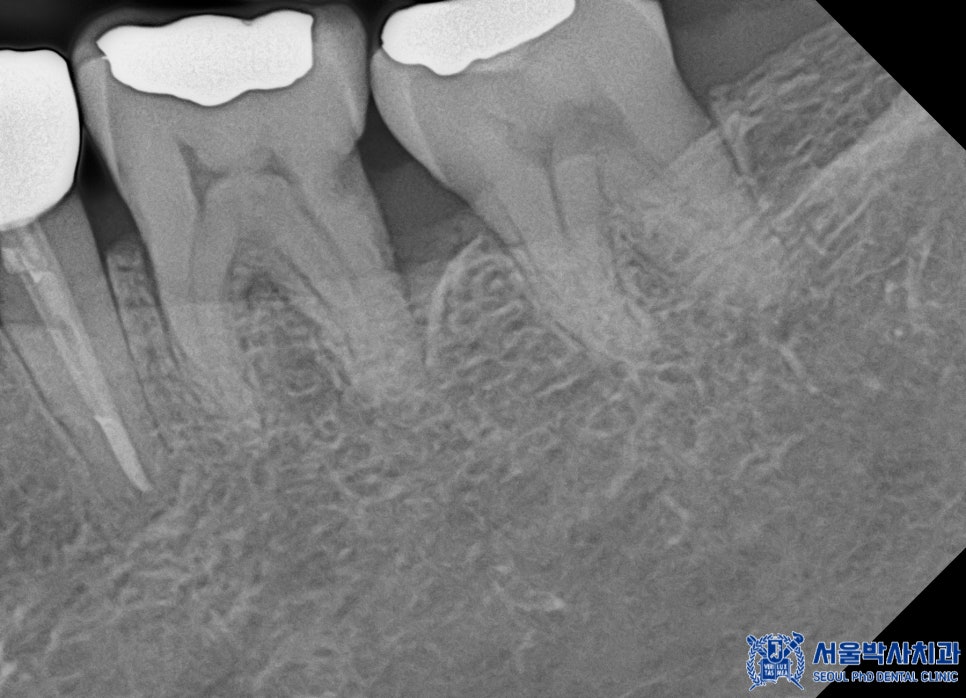

먼저 전체적인 검진 결과,

왼쪽 아래 큰 어금니 부위에서

금 인레이 아래쪽으로 이차 충치와

염증이 발견되었습니다.

해당 치아는 신경 치료가

필요한 상태였기 때문에

서울박사치과에서는

자연치아 보존을 최우선으로 하는

“MTA 신경치료”를 진행하기로 하였습니다.